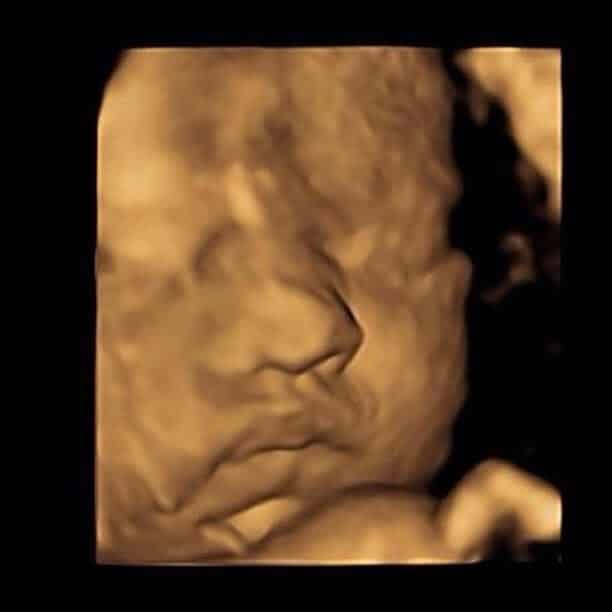

“It was a pleasure to welcome Rosie, Gemma and their daughter to our clinic so they could have their full well-being check and see their baby in 4D. It was so lovely to be able to share the experience with them. Despite baby not being in the best of positions at first, after a walk we were able to achieve some fabulous images and we’re pleased they enjoyed their experience and felt so welcome. We’re excited to see photos of baby when they’re born!” – Amy, Exeter Clinic Manager

Baby is as cute as a button!